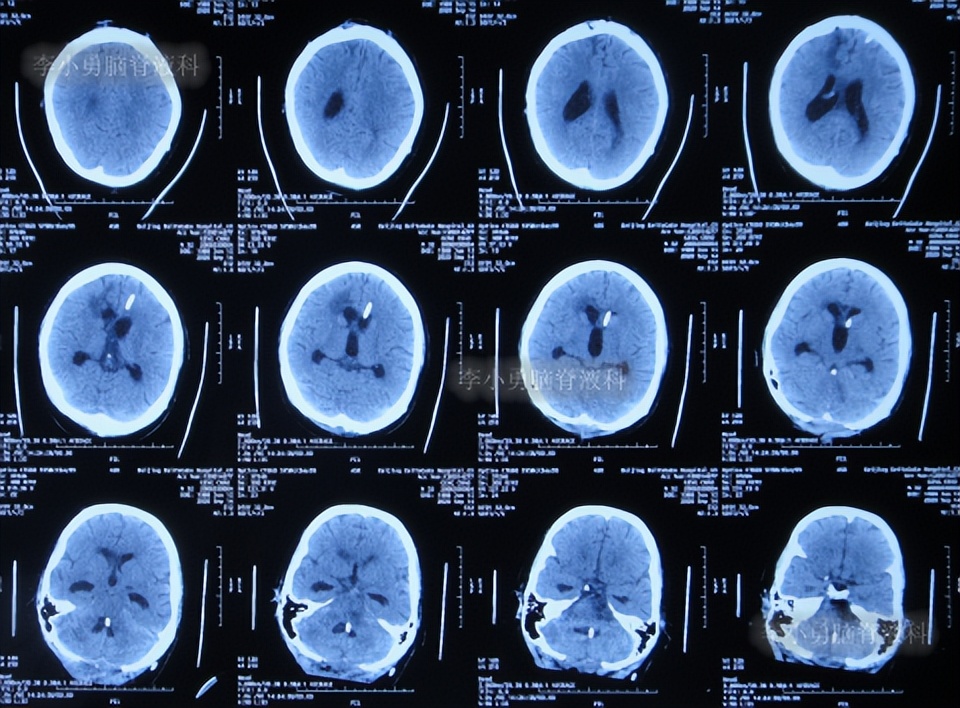

夹闭引流管后10天左右,脑室未扩张,于是拔除了侧脑室和颞角的引流管,进行了脑室腹腔分流术。

2022年11月15日(李小勇脑脊液科治疗151天)出院,出院时:意识正常,言语交流基本正常,自己走路差点(图-60);头颅CT示未见异常(图-61)。

图-60:2022年11月15日

图-61:出院时头颅CT